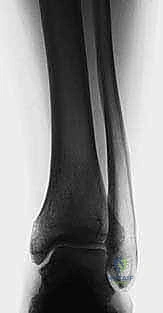

1. التخطيط الجراحي الدقيق (Pre-operative Planning)

يتم إجراء صور أشعة سينية خاصة (طويلة للساق بالكامل أثناء الوقوف) وأشعة مقطعية (CT Scan) ثلاثية الأبعاد. يقوم الدكتور محمد هطيف باستخدام برامج حاسوبية متقدمة لحساب الزاوية الدقيقة للتشوه، وتحديد حجم "الوتد العظمي" (Bone Wedge) الذي يجب إزالته أو إضافته لإصلاح المحور.